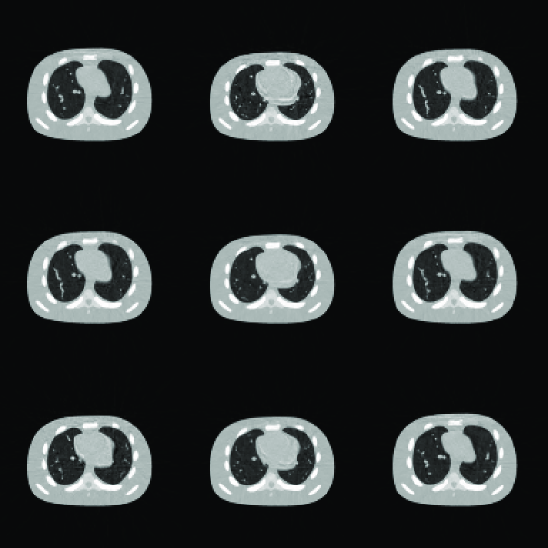

2.4 Experiments

We tested our cine-CBCT reconstruction algorithm on a digital NURBS-based cardiac-torso (NCAT) phantom (?), which generates a patient body in thorax region with detailed anatomical features and a realistic motion pattern. The patient respiratory period is 4 seconds. The CBCT gantry rotates about the patient at a constant speed for a full rotation in 59 seconds, in which 360 X-ray projections are acquired. At each X-ray projection acquisition, we compute the NCAT phantom image at the specific time point with a resolution of 128×128128128128\times 128, and the projection is then computed using a ray-tracing algorithm at the associated projection angle with a detector resolution of 256 bins. The patient breathing period and the gantry rotation period are chosen to be incommensurate deliberately, so that all the 360 patient images are distinct, although some of them visually look close. Some of the underlying true images are shown in Figure 1. Under this setup, the size of 𝑼𝑼\bm{U} is 16384×3601638436016384\times 360, and the size of 𝑭𝑭\bm{F} is 256×360256360256\times 360.

Refer to caption

Figure 1: The ground truth cine-CBCT images. From left to right, top to bottom: frame 40,80,,360408036040,80,\ldots,360.